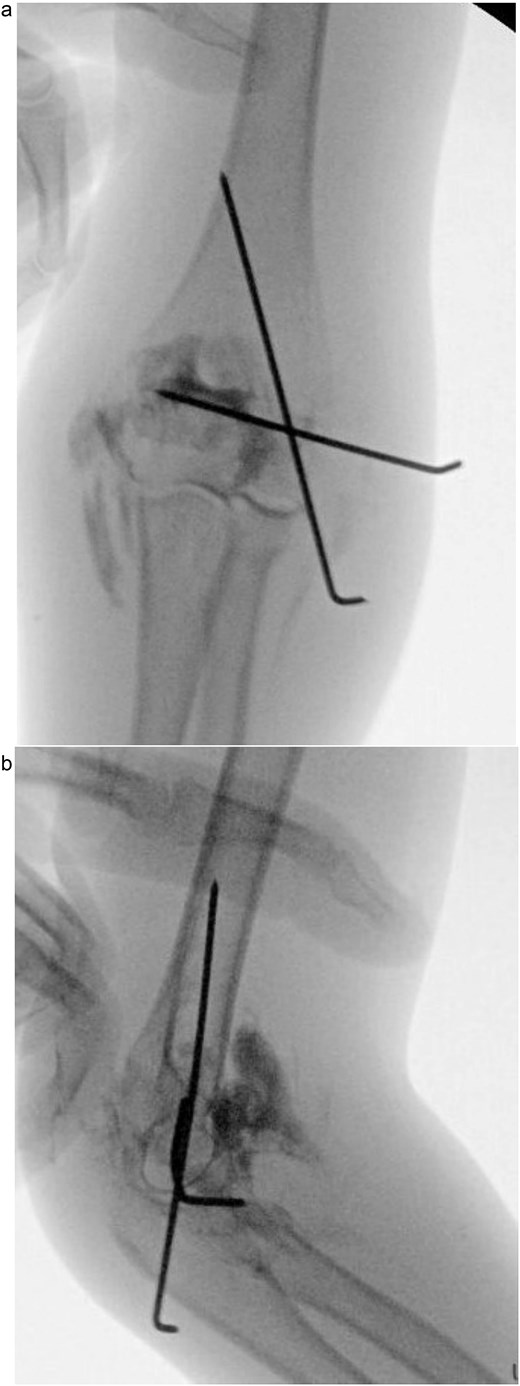

(a) Intraoperative fluoroscopic image following closed reduction and K-wire fixation showing anatomical alignment of the lateral condyle. (b) Arthrogram confirming a congruent articular surface and stable fixation of the fracture fragment.

(a) Postoperative anteroposterior radiograph demonstrating stable fixation of the lateral condyle with two smooth Kirschner wires. (b) Lateral view showing proper wire placement and a well-aligned elbow maintained in a posterior slab splint.